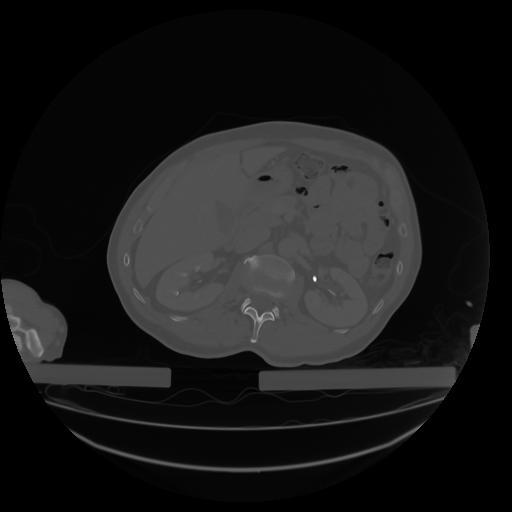

27 CUERPO,CE,Axial,3.0,CUERPO,,